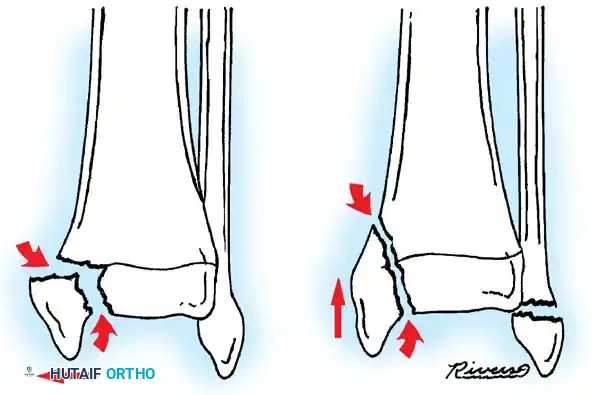

PROXIMAL TIBIAL METAPHYSEAL FRACTURES AND VALGUS DEFORMITY

Displaced fractures of the proximal tibial metaphysis carry a risk of posterior tibial artery injury. However, even non-displaced or minimally displaced metaphyseal fractures are notorious for a delayed complication: progressive valgus angular deformity, commonly known as Cozen's phenomenon.

Clinical Pearl: An incomplete metaphyseal fracture of the proximal tibia (often termed a "coaxing" or "trampoline" fracture) is highly worrisome. Even when minimally displaced, it carries a notorious reputation for developing a progressive valgus deformity (Cozen's phenomenon) during the healing phase.